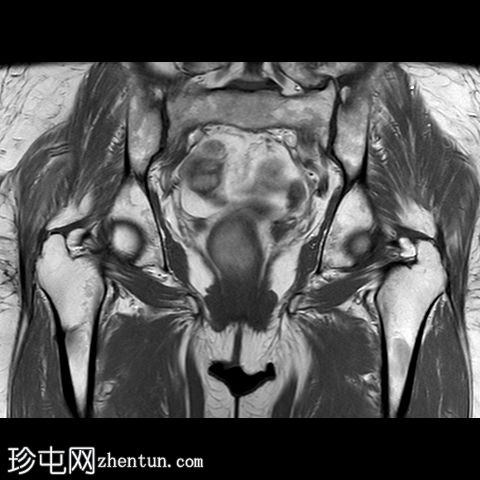

冠状位

T2

一条水平T1和T2低信号骨折线横断右股骨干外侧皮质。近1/3的骨干周长受累,并伴有邻近骨髓水肿。其余皮质骨完整。左股骨未见异常。

该患者有长期服用双膦酸盐类药物的病史,这是众所周知的股骨功能不全性骨折的危险因素。不完全性骨折会影响股骨外侧皮质,如本例所示,应立即治疗,否则可能发展为完全性骨折。治疗方案包括立即停用双膦酸盐类药物并进行髓内钉固定。由于此类骨折通常是双侧的,因此应始终对对侧股骨进行影像学检查。